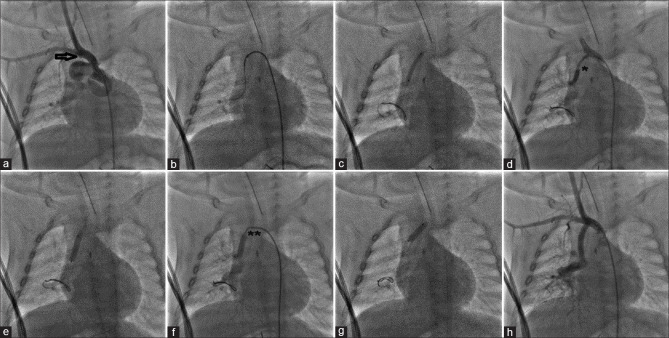

The modified Blalock-Taussig-Thomas shunt (mBTT shunt) is an effective palliation for cyanotic congenital heart diseases. However, a late obstruction of the mBTT shunt may present as a life-threatening complication. In this setting, a redo-surgery or a transcatheter recanalization is necessary to restore adequate pulmonary blood flow. We report three cases of transcatheter recanalization and stenting of a completely obstructed mBTT shunt, highlighting the tips and tricks of the percutaneous approach.

Abstract Image